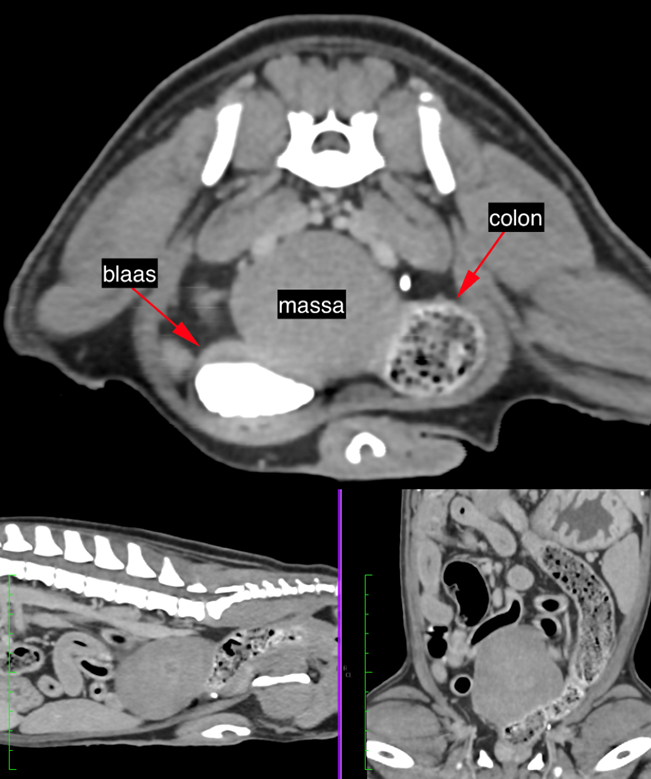

CT-onderzoek toont een hypoattenuerende massa caudaal in het abdomen met een massa-effect op de dunne darmen naar craniaal, het colon naar ventraal en naar links, en op de urineblaas naar ventraal en naar rechts. De massa heeft een gering heterogene structuur en geringe heterogene contrastmiddelopname. De massa lijkt met een smalle basis verbonden met de buitenste laag van de wand van het colon (fig 2).

Fig 2. Post-contrast transversaal CT-beeld en sagittale en dorsale MPR toont de massa caudaal in het abdomen met contact met blaas en colon. Er is een smalle basis zichtbaar met de wand van het colon op het transversale beeld.

Op basis van het CT-onderzoek wordt geconcludeerd: weke delenmassa in het caudale abdomen, vermoedelijk een excentrische tumor uitgaande van de wand van het colon, zonder zichtbare abdominale of pulmonale metastasen.